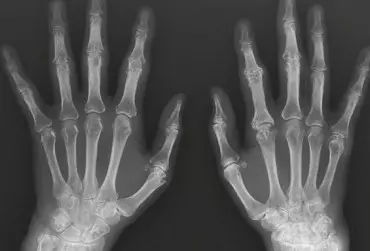

Czym jest zespół cieśni nadgarstka, jakie daje objawy i czy to na pewno on?  Większość pacjentów, a właściwie wszyscy, którym zaczęły dokuczać dolegliwości takie jak drętwienie dłoni, po wpisaniu tego hasła w wyszukiwarkę internetową dostają prostą i szybką odpowiedź: „Twoje dolegliwości to zespół cieśni nadgarstka”. „Wszystkie objawy pasują, a więc to musi być to” – pomyśli pacjent. Jakie więc objawy będzie zgłaszał pacjent?  Przede wszystkim drętwienie dłoni oraz palców. W przypadku zespołu cieśni nadgarstka istotne jest to, które palce drętwieją. Drętwienie będzie zatem dotyczyć kciuka, palców pierwszego, drugiego i trzeciego, a dokładniej jego połowy po stronie dłoniowej. Nerw pośrodkowy unerwia także końcówki wcześniej wymienionych palców, zachodząc delikatnie na część grzbietową.  Kolejnym niepokojącym objawem zgłaszanym przez pacjenta będzie brak siły dłoni. Dysfunkcja ta będzie się objawiać brakiem możliwości zaciśnięcia dłoni w pięść lub utrzymania przedmiotu, i nie chodzi tutaj o rzeczy ciężkie do utrzymania w ręce.  Zmiana temperatury palców, drętwienie oraz mrowienie w nocy, uczucie niepokojącej bolesnej sztywności palców, szczególnie nad ranem – to kolejne objawy, które będą budzić niepokój wśród pacjentów. Ale czy aby na pewno to zespół cieśni nadgarstka?  Należy pamiętać, że nie wszystkie wymienione tu objawy występują razem. Często są to także pojedyncze, incydentalne, ale w jakiś sposób powtarzalne dolegliwości. Przykładem może być uczucie sztywności oraz tkliwości w obszarze nadgarstka czy też przedramienia lub samo drętwienie palców w trakcie snu. Mimo wszystko te objawy pokierują pacjenta do neurologa w celu wykonania badania przewodnictwa nerwowego, jakim jest badanie EMG. Bywa i tak, że – jak w wielu badaniach obrazowych – wynik pacjenta jest negatywny, a dokładniej rzecz ujmując, nie stwierdza się żadnego typu patologii. W przypadku badania EMG pacjent dostanie wynik, w którym będą podane wartości prawidłowe dla przewodnictwa nerwowego.  Jeśli to nie zespół cieśni nadgarstka, to co zatem może być przyczyną tego typu dolegliwości? Braki witamin z grupy B? Deficyt magnezu, potasu lub witaminy D3? Odwodnienie lub przeciążenie dłoni pacjenta przez ciężką pracę fizyczną? A może padnie diagnoza typu „to na pewno od kręgosłupa”? Tu pojawia się jakże istotna kwestia – obszerny wywiad z pacjentem, w opinii autora najistotniejsza, a zarazem najtrudniejsza część wizyty dla terapeuty manualnego czy też neurologa. Wywiad jest jednak tą częścią wizyty, w trakcie której uzyskuje się wiele cennych informacji na temat pacjenta. Oprócz samego wywiadu równie istotna jest ocena postawy oraz wykonanie przynajmniej kilku podstawowych testów badających zakresy ruchomości lub testów celowanych w kierunku dysfunkcji poszczególnych nerwów.  Czy postawa pacjenta będzie mieć wpływ na drętwienie dłoni? Przed przystąpieniem do dokładnego opisu przebiegu nerwu pośrodkowego warto, a nawet trzeba wspomnieć o samej postawie pacjenta, ponieważ ma ona bezpośredni związek z zespołem cieśni nadgarstka lub objawami podobnymi do ZCN (zespołu cieśni nadgarstka). Postawa ciała pacjenta jest bardzo istotna w kwestii analizowania oraz diagnozowania wielu dysfunkcji i absolutnie nie można o tym zapominać. Na co należy zwrócić szczególną uwagę w trakcie przeprowadzania wywiadu z pacjentem? Co powinno zaniepokoić i co trzeba przeanalizować w szczegółowy sposób?  W pierwszej kolejności należy odpowiedzieć sobie na pytanie, czym jest postawa ciała. Postawa ciała jest formą adaptacji organizmu człowieka do warunków, w jakich przebywa. A więc postawa jest niejako odzwierciedleniem kondycji psychofizycznej. Pacjenci z jaką postawą będą narażeni na ZCN? Bezsprzecznie wszyscy ci, którzy mają zamkniętą klatkę piersiową, ramiona oraz głowę ustawioną w protrakcji. Takiemu ustawieniu kręgosłupa szyjnego oraz piersiowego bardzo często towarzyszy ustawienie kończyn górnych w nadmiernej rotacji wewnętrznej. Biorąc pod uwagę przebieg nerwu pośrodkowego, jest to bardzo istotna informacja. Taki rodzaj postawy ciała pacjenta powinien zapalać czerwoną lampkę w głowie terapeuty już na samym początku. Jeśli pacjent zgłasza objawy takie jak drętwienie, mrowienie dłoni, osłabienie siły chwytu czy też inne problemy charakterystyczne dla zespołu cieśni nadgarstka, ale ewidentnie ma problem z postawą ciała i elastycznością poszczególnych, istotnych dla przebiegu nerwu pośrodkowego struktur, koniecznie należy przeprowadzić dokładną analizę przebiegu nerwu pośrodkowego.  I oto najistotniejsze miejsce tego artykułu, a więc dokładny opis przebiegu nerwu pośrodkowego oraz opis poszczególnych technik pracy z tą strukturą. Poznanie jego przebiegu pokaże, że problem może tkwić na różnych poziomach!  Dlaczego wiedza na temat dokładnego przebiegu nerwu pośrodkowego jest aż tak istotna? Dobra znajomość anatomii daje wiele możliwości pracy z pacjentem. Dlaczego? Ponieważ terapeuta nie ogranicza się do wykonywania „standardowych” technik przypisanych danej dysfunkcji. Zaczyna widzieć i rozumieć więcej połączeń oraz zależności. Jedną z przykładowych dysfunkcji pokazujących, że nie warto ograniczać się jedynie do jednego segmentu, jakim jest kręgosłup szyjny lub kanał nadgarstka, jest właśnie zespół cieśni nadgarstka.  Gdy u pacjenta pojawią się typowe dla tej dysfunkcji dolegliwości, szybko zaczyna się szukać problemu w odcinku szyjnym kręgosłupa lub w okolicy nadgarstka. Czy jest to złe czy też niewłaściwe podejście? Nie, ale w pewnym stopniu bardzo ograniczające możliwości pracy z pacjentem. Dlaczego? Ponieważ gałązka nerwu pośrodkowego jest długą strukturą, na którą – jak się za chwilę okaże – ma wpływ wiele rzeczy.  Na początek należy zwrócić uwagę, jak w stosunku do innych tkanek funkcjonują struktury nerwowe. Gałązka nerwowa – i dotyczy to każdego nerwu – jest strukturą słabo modelującą. Co to znaczy? Nie jest strukturą rozciągliwą, a więc już wiadomo, że do prawidłowego funkcjonowania musi mieć zapewniony odpowiedni ślizg międzytkankowy. Niestety, często zostaje uwięziona między poszczególnymi strukturami. Zaburzenie ślizgu gałązki nerwowej będzie w negatywny sposób wpływać na jej biomechanikę, co często będzie przyczyną różnego typu dolegliwości takich jak mrowienie czy drętwienie.  Wracając do przebiegu samego nerwu pośrodkowego, jego przebieg zostanie opisany za pomocą stacji. Na początek oczywiście stacja pierwsza, która jest bardzo istotna w pracy z pacjentem.  Stacja pierwsza  Stacja pierwsza będzie dotyczyć segmentów odcinka szyjnego kręgosłupa. Dlaczego? Ponieważ nerw pośrodkowy otrzymuje włókna z segmentów C6, C7, C8 oraz Th1. Zmiany na tej wysokości kręgosłupa, widoczne w badaniu obrazowym, mogą sugerować, że to właśnie na tym poziomie zaczyna się problem drętwienia dłoni. Oczywiście za chwilę zostaną opisane kolejne stacje, niemniej jednak w całym procesie leczenia zespołu cieśni nadgarstka nie można pomijać żadnej stacji, a więc warto, a nawet trzeba zweryfikować sytuację na wysokości odcinka szyjnego kręgosłupa. Podsumowując stację pierwszą, warto sprawdzić napięcie tkanek w obszarze szyi oraz karku, a także zbadać poszczególne zakresy ruchomości odcinka szyjnego pacjenta.  Stacja druga Drugą stacją będzie przednio-boczna część szyi, a dokładniej obszar, w którym znajdują się mięśnie pochyłe. Dlaczego ten obszar jest równie istotny? Mięśnie pochyłe to grupa trzech mięśni: pochyły przedni, środkowy oraz tylny. Są to specyficzne mięśnie, ponieważ przyczepiają się do kręgosłupa szyjnego oraz żeber. Pełnią funkcję zgięcia bocznego czy też ruchu rotacyjnego, dlatego informacja o tym, że przyczepiają się do żeber, jest szalenie istotna! Dlaczego? Ponieważ mięśnie pochyłe będą w pewnym stopniu ustawiać pierwsze oraz drugie żebro w przestrzeni, a więc będą miały wpływ na relację pierwszego oraz drugiego żebra w stosunku do obojczyka. Ustawienie żeber w elewacji, czyli uniesieniu, będzie zmniejszać przestrzeń między pierwszym i drugim żebrem a obojczykiem. Oczywiście ta przestrzeń jest zarezerwowana dla pęczka nerwowo-naczyniowego. Kompresja w tym obszarze może być więc przyczyną drętwienia dłoni.  Podsumowując, w przypadku stacji drugiej koniecznie należy zweryfikować napięcie w tym obszarze, a więc gdy wystąpi potrzeba, należy opracować mięśnie pochyłe, a także pomóc żebrom wrócić do pierwotnej pozycji.  Stacja trzecia Stacja trzecia to obszar podobojczykowy. W tym momencie warto wspomnieć o małym, ale jakże istotnym mięśniu podobojczykowym, mięśniu piersiowym mniejszym oraz mięśniu kruczo-ramiennym. Wymienione struktury mięśniowe również będą wpływać na pęczek nerwowo-naczyniowy. Bardzo mały, ale jakże istotny mięsień podobojczykowy będzie ustawiać obojczyk w przestrzeni, a więc jego napięcie ma realny wpływ na pracę stawów barkowo-obojczykowego oraz mostkowo-obojczykowego. Łączy się z żyłą podobojczykową za pośrednictwem wspólnej powięzi.  Następnym mięśniem będzie mięsień piersiowy mniejszy. Przyczepia się do wyrostka kruczego łopatki i biegnie do III–V żebra, a czasem nawet do żebra VII, i jest to kwestia osobnicza różna. Końcowy przyczep mięśnia piersiowego mniejszego może się różnić nawet u tego samego pacjenta w zależności od strony, co niejednokrotnie można zobaczyć w trakcie warsztatów z anatomii sekcyjnej. To niesamowicie istotny mięsień, biorąc pod uwagę kilka faktów na jego temat. Jest mięśniem ustawiającym łopatkę w przestrzeni, a dokładniej jego nadmierne napięcie będzie ustawiać łopatkę w rotacji górnej. Z pozycji spionizowanej łopatka będzie przechodzić w niewłaściwe, pochylone ustawienie. Napięcie mięśnia piersiowego mniejszego będzie się przyczyniać do uwidocznienia kąta dolnego łopatki.  Kolejną, jeszcze ważniejszą informacją jest fakt, że pod mięśniem piersiowym mniejszym również znajduje się pęczek nerwowo-naczyniowy, a więc splot nerwowy, a także żyła oraz tętnica podobojczykowa przechodzące w żyłę oraz tętnicę pachową. Nadmierne napięcie mięśnia piersiowego mniejszego będzie więc gilotynować nerw pośrodkowy i nie tylko.  Następnym mięśniem, o którym nie można nie wspomnieć, będzie mięsień kruczo-ramienny, który wraz z mięśniem piersiowym mniejszym będzie tworzyć jeden łańcuch mięśniowo-powięziowy pod warunkiem ustawienia kończyny górnej pod odpowiednim kątem. Uniesienie ręki (jak do sięgania po coś lub jak do zwisu na drążku) będzie ustawiać te dwa mięśnie w jednej linii, czyli gałązka nerwu pośrodkowego zależy również od tego mięśnia. Przebiega tuż pod nim, więc jego nadmierne napięcie nie będzie wpływać na nią w korzystny sposób.  Podsumowując stację trzecią, należy starannie sprawdzić obszar podobojczykowy. Niewłaściwe ustawienie łopatki oraz nadmierne napięcie mięśnia piersiowego mniejszego to częsta przyczyna osłabienia siły kończyny górnej.  Stacja czwarta  Stacja czwarta kieruje się wzdłuż kończyny górnej. Tu należy wspomnieć o mięśniu dwugłowym ramienia oraz mięśniu trójgłowym ramienia, a dokładniej o przestrzeni między nimi, zlokalizowanej tuż nad stawem łokciowym. To właśnie w tej bruździe, dosyć płytko, będzie przebiegał nerw pośrodkowy.  Stacja czwarta to mały, ale bardzo istotny obszar. Warto zatrzymać się na chwilkę na tym poziomie, by zweryfikować palpacyjnie napięcie tkanek.  Stacja piąta  Nerw pośrodkowy dalej kieruje się w stronę przedramienia, nadgarstka oraz dłoni. Jednak tuż pod stawem łokciowym znajduje się kolejne bardzo istotne miejsce pod kątem terapii. Jest to obszar zajmowany przez mięsień nawrotny obły – charakterystyczny mięsień składający się z dwóch brzuśców przypominających nożyce. Jest to istotna informacja, zważywszy na fakt, że między dwoma brzuścami będzie przebiegać nerw pośrodkowy.  Dlaczego warto zwrócić szczególną uwagę na ten obszar? Ponieważ większość osób z problemem, jakim jest drętwienie dłoni, ma zamkniętą klatkę piersiową, kończyny górne ustawione w nadmiernej rotacji wewnętrznej – ustawienie ich w zgięciu (częściej widoczne u mężczyzn z racji większej masy mięśniowej), dotyczy to również przedramienia. Mięsień nawrotny obły pełni dwie funkcje – zgięcia w stawie łokciowym oraz nawracania w stawie promieniowo-łokciowym. Jego nadmierne napięcie będzie pozbawiać przedramię elastyczności właśnie na tym poziomie oraz trwale ustawiać przedramię w nieprawidłowej pozycji, co dla biomechaniki nerwu pośrodkowego nie będzie korzystną sytuacją.  Opracowanie stacji piątej nie będzie się ograniczać jedynie do poziomu mięśnia nawrotnego obłego. Należy zwrócić uwagę na elastyczność tkanek od poziomu nadgarstka aż do dołu łokciowego.  Stacja szósta  Stacja szósta jest pewną ciekawostką, opisem niepopularnej dysfunkcji w obszarze przedramienia. Dotyczy nerwu międzykostnego przedniego przedramienia. Jest to gałązka odchodząca od nerwu pośrodkowego, znajdująca się na błonie międzykostnej przedramienia, a więc bezpośrednio między kością promieniową oraz łokciową. Należy pamiętać, że klinicznie występuje taka dysfunkcja jak zespół nerwu międzykostnego przedniego przedramienia. Jej objawem będzie ból, dyskomfort w obszarze przedramienia, który może promieniować do okolicy nadgarstka, dłoni oraz przedramienia.  Możliwe, że objawy typowe dla ZCN wystąpią u pacjentów po przebytym złamaniu kości przedramienia. Uszkodzenie szkieletu będzie mieć istotny wpływ na napięcie błony międzykostnej, na której znajduje się nerw międzykostny przedni przedramienia. Warto więc zwrócić na ten obszar szczególną uwagę, zwłaszcza jeśli pacjent w wywiadzie zgłosi przebyty uraz tej okolicy.  Stacja siódma  Po przejściu przez mięsień nawrotny obły oraz pozostałe mięśnie przedramienia, a także błonę międzykostną czas na owiany złą sławą kanał nadgarstka. To właśnie na tej wysokości wykonuje się zabieg chirurgiczny w celu odbarczenia nerwu pośrodkowego. Oczywiście terapeuci manualni będą w tym miejscu szukać tkliwości, sztywności, napięcia, a także ograniczenia ruchomości nadgarstka.  Stacja ósma  Ostatnia, ósma stacja będzie dotyczyć pracy ze śródręczem oraz palcami. To właśnie do palców nerw pośrodkowy oddaje końcowe gałązki. Są to: kciuk, palce pierwszy, drugi oraz połowa trzeciego palca po stronie dłoniowej.  Na tej wysokości należy się skoncentrować na uwalnianiu napięć z obszaru unerwienia nerwów dłoniowych wspólnych palców oraz nerwów dłoniowych właściwych palców. Warto zwrócić uwagę na ten obszar szczególnie u osób wykonujących pracę dłońmi. Będą to zarówno pracownicy biurowi pracujący przed komputerem, jak i pracownicy fizyczni.  Podsumowanie Celem niniejszego artykułu było przedstawienie pracy z nerwem pośrodkowym, a także zwrócenie uwagi na fakt, iż pojawienie się objawów charakterystycznych dla danej dysfunkcji nie musi oznaczać, że to właśnie na nią cierpi pacjent. Terapeuci manualni muszą pamiętać, że wiele objawów często będzie podszywać się pod dysfunkcje, które należy leczyć zabiegowo lub farmakologicznie. Podstawą pracy każdego fizjoterapeuty powinien być obszerny wywiad oraz dokładna analiza pacjenta.

Diagnostyka różnicowa zespołów bólowych kończyny górnej. Część 2

Dolegliwości bólowe w obrębie kończyny górnej mogą mieć różną przyczynę, dlatego tak ważna jest diagnostyka różnicowa. W ustaleniu prawidłowego rozpoznania pomocne jest tradycyjne badanie radiologiczne, które pozwala na wykrycie wielu patologii, takich jak urazy, zmiany zwyrodnieniowe, przeciążeniowe, choroby metaboliczne, zapalne i nowotwory, choć ma też swoje ograniczenia.

Diagnostyka różnicowa zespołów bólowych kończyny górnej. Część 1

Kończyna górna w procesie ewolucyjnym człowieka z roli podporowej przekształciła się w narzędzie chwytne, zdolne do ruchów o wysokiej precyzji. Procesowi temu towarzyszyć musiały zmiany anatomii samej kończyny (pojawiły się mniej masywne kości, ale bardziej ruchome stawy z licznymi drobnymi mięśniami ręki), a także rozwój układu nerwowego, dzięki któremu człowiek może korzystać w pełni z możliwości tak doskonałego mechanizmu, jakim jest ludzka ręka. Ceną za tę ścieżkę rozwoju jest jednak zwiększone ryzyko urazów i przeciążeń kończyny górnej.